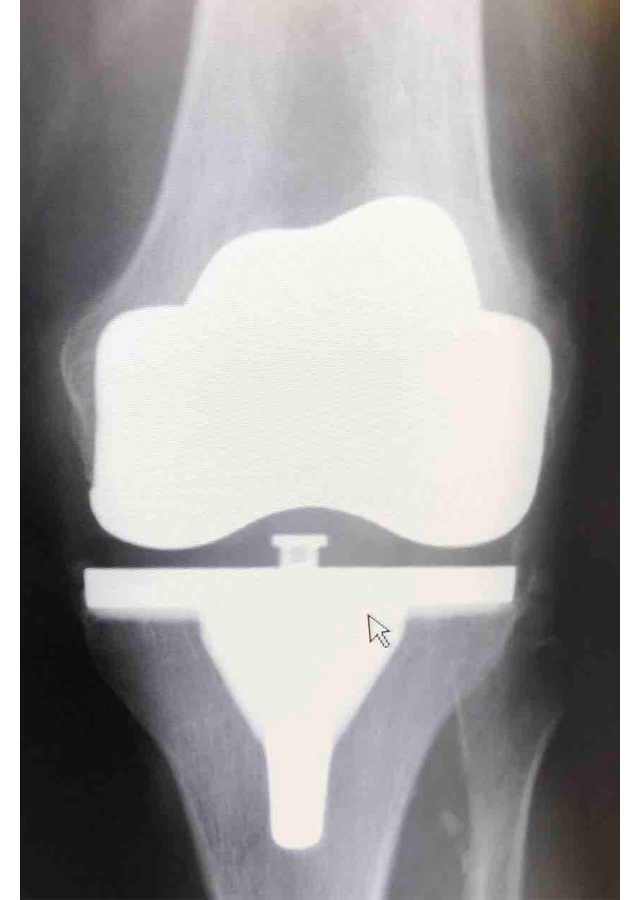

Csípő és térd ízületi betegségek protetizálása

Degeneratívtól, posttraumáson át veleszületett deformitásokig, revíziók, egyszerű és bonyolult helyzetek megoldása.